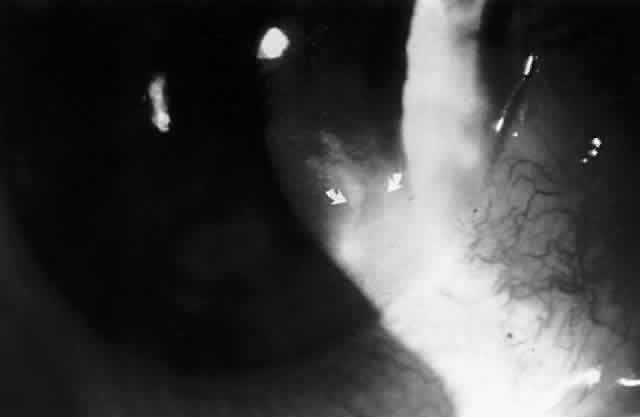

In 1990, Pflugfelder and associates reported a 66-year-old woman with bilateral, pleomorphic, ring-shaped, anterior stromal opacities which developed 3 months after initial onset of concurrent bilateral, dendritic epithelial keratitis (Fig. 5).74 Dendritic epithelium removed by impression cytology at the second recurrence of epithelial disease bound monoclonal antibody to EBV early antigen-diffuse and contained EBV genomic sequences as shown by PCR. Corneal epithelial cultures for HSV were negative on two occasions. EBV serology test did not indicate acute infection, and thus confirmed the earlier impression of Matoba and associates, that EBV keratitis may follow viral reactivation from the chronic carrier state.

Fig. 5. Peripheral corneal dendrite (arrows) in a 66-year-old woman who later developed ring opacities of the anterior corneal stroma.